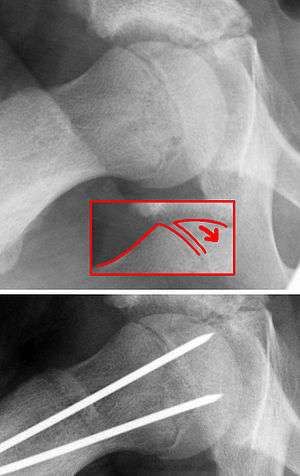

| X-ray showing a slipped capital femoral epiphysis, before and after surgical fixation. | |

The diagnosis requires x-rays of the pelvis, with anteriorposterior (AP) and frog-leg lateral views.[7] The appearance of the head of the femur in relation to the shaft likens that of a "melting ice cream cone", visible with Klein's line. The severity of the disease can be measured using the Southwick angle.

The disease can be treated with external in-situ pinning or open reduction and pinning. Consultation with an orthopaedic surgeon is necessary to repair this problem. Pinning the unaffected side prophylactically is not recommended for most patients, but may be appropriate if a second SCFE is very likely.[7]

Once SCFE is suspected, the patient should be non-weight bearing and remain on strict bed rest. In severe cases, after enough rest the patient may require physical therapy to regain strength and movement back to the leg. A SCFE is an orthopaedic emergency, as further slippage may result in occlusion of the blood supply and avascular necrosis (risk of 25 percent). Almost all cases require surgery, which usually involves the placement of one or two pins into the femoral head to prevent further slippage.[8] The recommended screw placement is in the center of the epiphysis and perpendicular to the physis.[9] Chances of a slippage occurring in the other hip are 20 percent within 18 months of diagnosis of the first slippage and consequently the opposite unaffected femur may also require pinning.

The risk of reducing this fracture includes the disruption of the blood supply to the bone. It has been shown in the past that attempts to correct the slippage by moving the head back into its correct position can cause the bone to die. Therefore the head of the femur is usually pinned 'as is'. A small incision is made in the outer side of the upper thigh and metal pins are placed through the femoral neck and into the head of the femur. A dressing covers the wound.